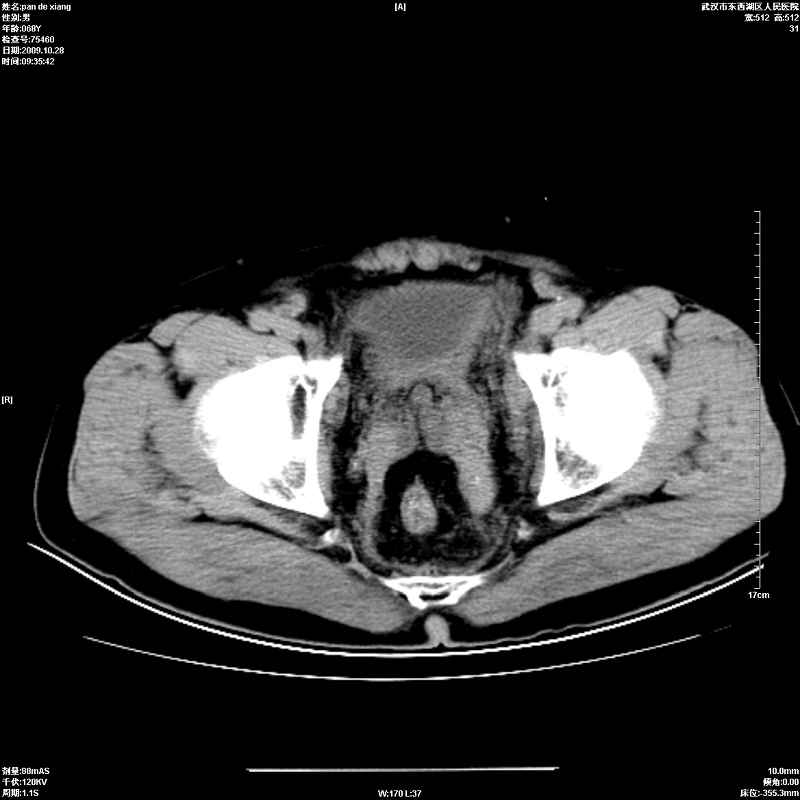

以下是引用杀毒软件在2009-10-28 20:41:00的发言:[br]结合临床考虑---白血病双肾改变或淋巴瘤。

以下是引用zxl51642在2009-10-29 9:59:00的发言:[br]结合临床“单克隆免疫球蛋白血症”,考虑双肾为继发损害并肾功能不全(尿中大量igg及少量iga、igm等大分子免疫球蛋白滤出所致继发损害),椎前软组织肿块为髓外造血。与浆细胞瘤有区别,平扫时有战友说的很清楚。